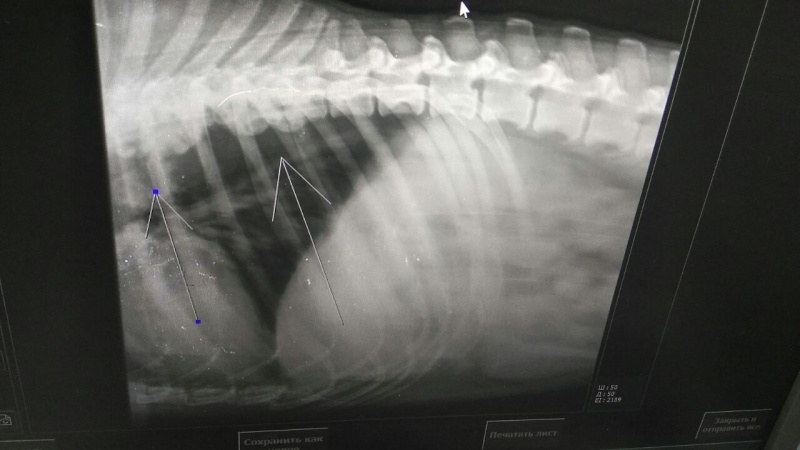

Сделали рентген. Все не очень хорошо, мягко сказано. Диагноз : спондилоартроз 3-ей степени. Дегенративно-дистрофические изменения позвонков. Собак с этим диагнозом ,как правило, усыпляют.

Прогноз осторожный в сторону неблагоприятного ( может остаться инвалидом). Врачи советуют не мучить собаку.